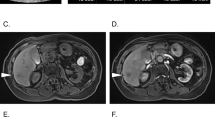

Case 2

A 40-year-old female patient had suffered from upper quadrant abdominal pain, with occasional nausea and fever for more than 2 years. The patient was diagnosed as cholecystitis at another hospital nearby and felt relieved very soon after treatment in the past 2 years. She came to the hospital 11 days ago due to the severe upper quadrant abdominal pain recurred with severe jaundice. Complete medical examinations, including blood pressure, pulse rate, temperature and physical examination of the abdomen, were performed in the Fifth Affiliated Hospital of Sun Yat-sen University. The clinical examinations revealed that the pulse rate, temperature and blood pressure were normal. Stool microscopy for parasite eggs by direct smear method were negative 3 times. Computed tomography (CT) scan revealed obstruction of the bile duct with dilation of the intrahepatic ducts which suggested a retained bile duct stone and a gallbladder stone (Fig. 3). Laboratory data indicated obstruction jaundice, peripheral eosinophilia and liver enzymes elevation (Table 1). Detailed inquiry revealed she had a history of eating raw freshwater fish. A clinical diagnosis of acute cholangitis and cholecystitis was made and laparoscopic cholecystectomy and laparoscopic common bile duct exploration was performed. Many flat, leaf-like worms appeared under the choledochoscope as deep bile duct cannulation (Fig. 4 and Fig. 5). Besides, many nodules distributed dispersedly among the surface of the liver (Fig. 6). After the operation, the“T” shape catheter was placed in the common hepatic duct to allow patent drainage. The patient was treated with anthelmintic therapy (albendazole: 16 mg/kg/day for 4 days). More C. sinensis worms were drained through the “T” shape catheter (Fig. 7). The clinical status of the patient improved gradually without the pain recurring.

Fig. 5

Choledochoscope view of worms inside the bile duct

Fig. 6

Nodules (indicated by arrows) distributed on the surface of the liver